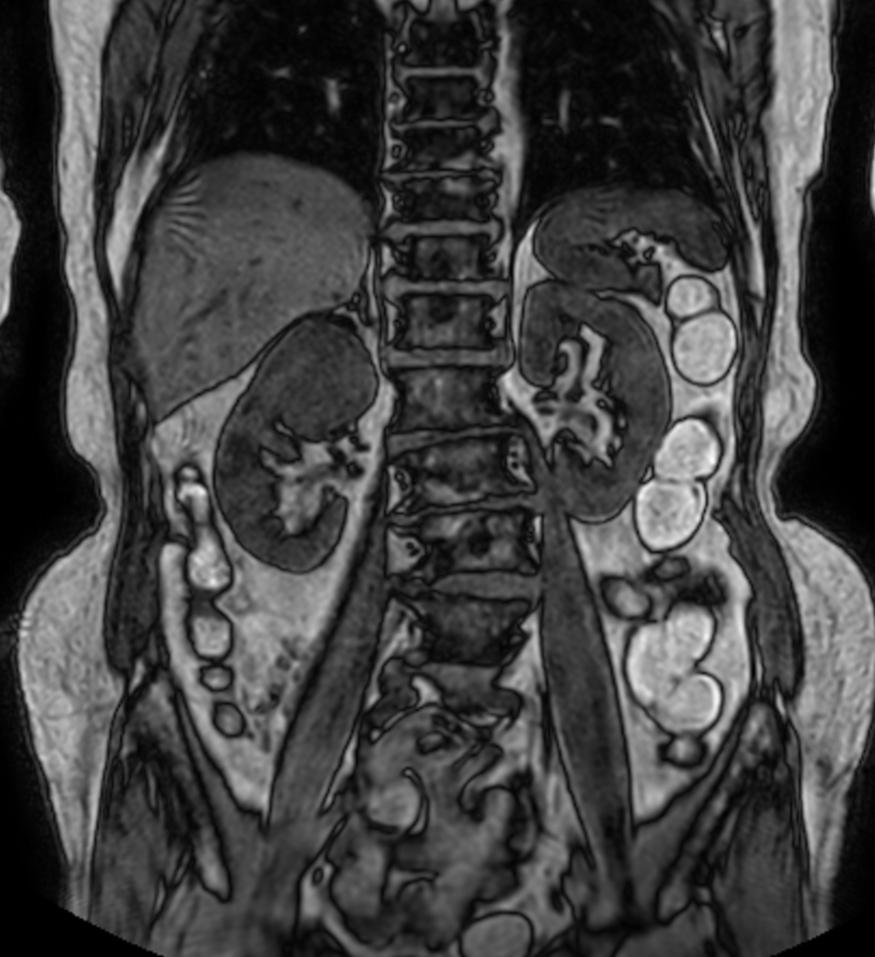

Patient with a kidney lesion. The ExamCard includes techniques for 3D imaging (PelvisVIEW, eTHRIVE) allowing for multiple image directions in one single scan, efficient fat-free imaging over large field-of-views (mDIXON XD), a multi-phase contrast-enhanced sequence (4D FreeBreathing) to improve imaging confidence and Compressed SENSE to accelerate the entire exam.

T2w TSE